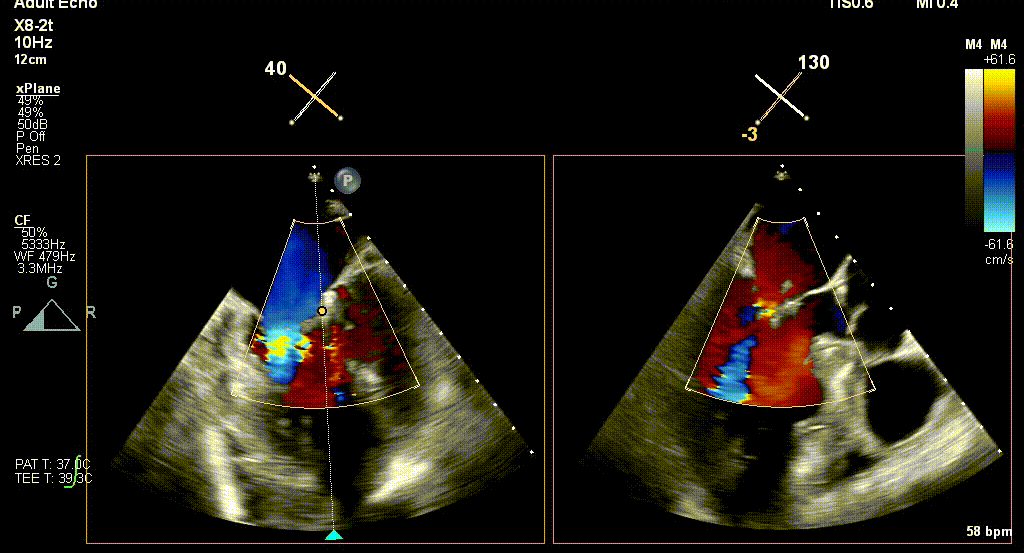

经食道超声引导后,王建安教授将二尖瓣夹NTR夹取C1区瓣叶,准确成功捕获C1前叶和后叶反流最严重区域,并予夹合。使二尖瓣在收缩期由大的单孔变成一大一小的双孔,显著减少了二尖瓣反流。

反复测试二尖瓣夹的稳定性,食道超声复查提示二尖瓣夹C1区反流有效改善,术后反流量由术前的4+变为术后的<1,遂精准释放二尖瓣夹。